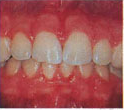

Comparison of healthy and diseased gums

Healthy gums Diseased gums

Healthy gums are pink in color Diseased gums are red in color

They are firm in consistency They are firm in consistency

They never bleed These bleed on slightest provocation

Their appearance is stippled Their appearance is plane